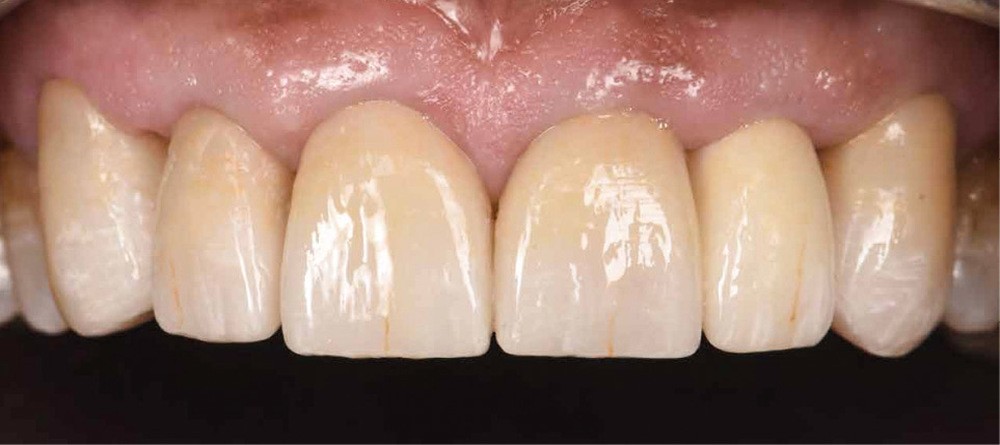

Le prothésiste réalise six RACCs en vitrocéramique renforcée au disilicate de lithium en technique pressée. Des caractérisations sont présentes pour mimer l’usure physiologique (fig. 5). Une chape « Haute Opacité » (HO) permettra de masquer l’effet grisâtre de l’inlay-core (fig. 6).

La troisième et dernière étape consiste en la réalisation du collage des RACCs via un protocole de collage strict, précédée par la vérification de l’ajustage des pièces (fig. 7) : l’isolation est primordiale via l’utilisation d’un champ opératoire médium, de ligatures et bandes en téflon (fig. 8 et 9) ainsi que de crampons B4 (fig. 10) pour exposer les limites de préparations. La validation de l’occlusion statique et dynamique est réalisée, suivie par un polissage soigneux des limites (fig. 11).

Le rapport de ce cas clinique permet d’illustrer certaines techniques modernes (planification esthétique informatisée, mock up) qui, couplées au progrès des matériaux et des techniques de collage, assurent un bon pronostic aux restaurations. La communication est au centre de nos thérapeutiques : que ce soit entre le praticien et le patient ou entre le praticien et le prothésiste. Ces derniers sont de véritables artistes céramistes à qui il faut donner tous les outils nécessaires. Nous devons également raisonner nos patients. « Envisager l’équilibre harmonieux comme la somme de déséquilibres. »